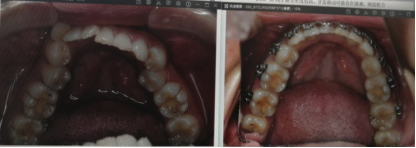

医院提供的口腔医疗项目丰富多样,包括牙齿美白、儿童牙科、烤瓷牙、拔牙、牙齿矫正、口腔预防保健和洗牙等。以下为大家简单介绍部分项目价格:

还有 陈振明 医生,作为执业医师,同样有10多年的牙科诊疗经验。他擅长牙齿矫正、牙齿美容、牙齿治疗、种植牙、牙齿修复等。陈医生毕业于广西医 科 大学,是韩国AIC种植进修培训医师,还多次参加国内外整形学术交流会学习,治疗技术不错,深受患者好评。